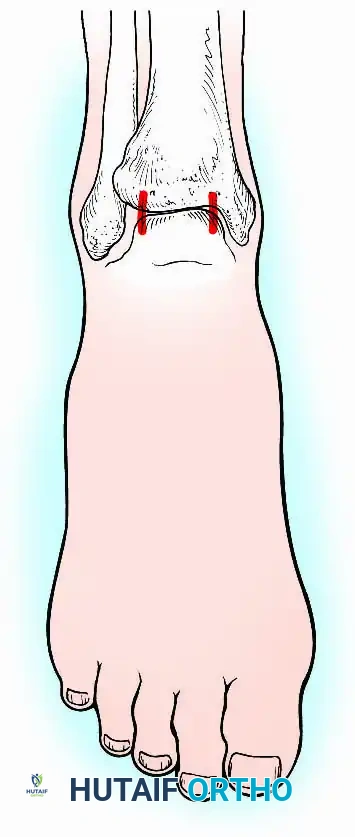

Historically pioneered by Charnley, external compression arthrodesis utilizes pins placed through the distal tibia and the body of the talus. Because Charnley's original uniplanar device lacked rotatory stability, Calandruccio designed a triangular frame to control motion in all three planes while applying massive compression.

Modern iterations, such as the Calandruccio II compression device, offer greater latitude in pin placement to avoid compromised skin. Ring or circular external fixators (Ilizarov, Taylor Spatial Frame) are the gold standard for salvage situations, including active infection, massive bone loss, or failed TAA, as they allow for simultaneous compression, deformity correction, and early weight-bearing.